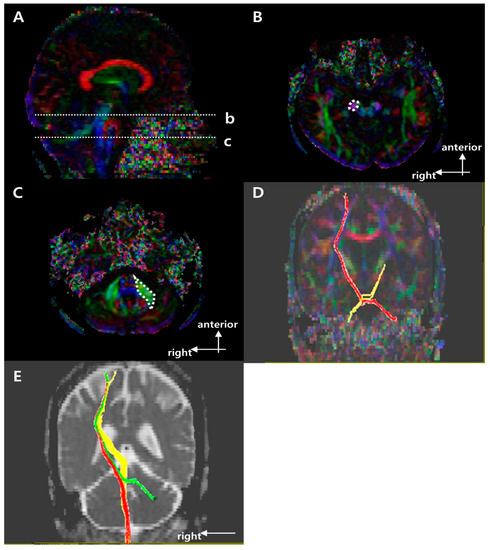

2.3. Fiber Bundle Tracking